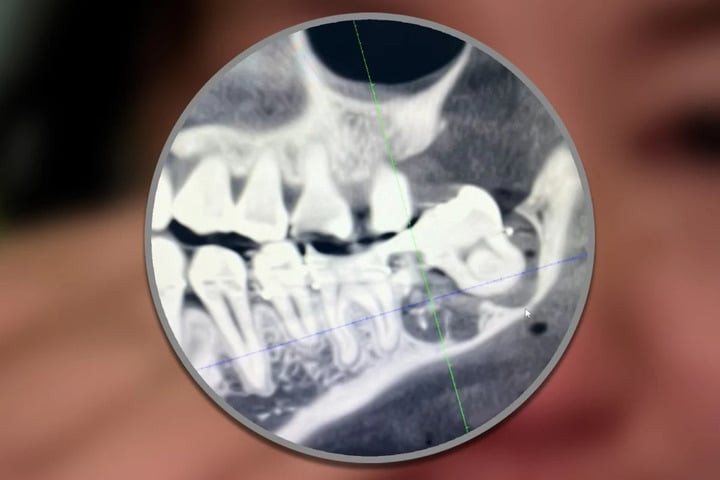

Các bác sĩ nhổ nhầm răng hàm bên cạnh chiếc răng khôn của Wu.